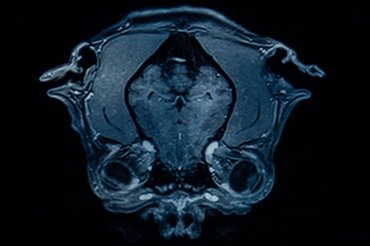

A kérdés megválaszolásához sok kutyának az agyára és azok méréseire van szükség. Szerencsére Csörgő Tibor az ELTE Anatómiai, Sejt- és Fejlődésbiológiai Tanszékén évtizedek óta gyűjti ezeket a koponyákat. Egészen pontosan az azokról készült CT-vizsgálatok felvételeit. Ez alapján és még néhány számítást követően sikerült rekonstruálni az agyakat és meghatározni azok pontos térfogatát. A kutatócsoport egy 865 ebből álló adatbankot hozott létre 159 kutyafajtára kiterjedően, valamint további 48 farkast ábrázoló felvétellel is kiegészítve.